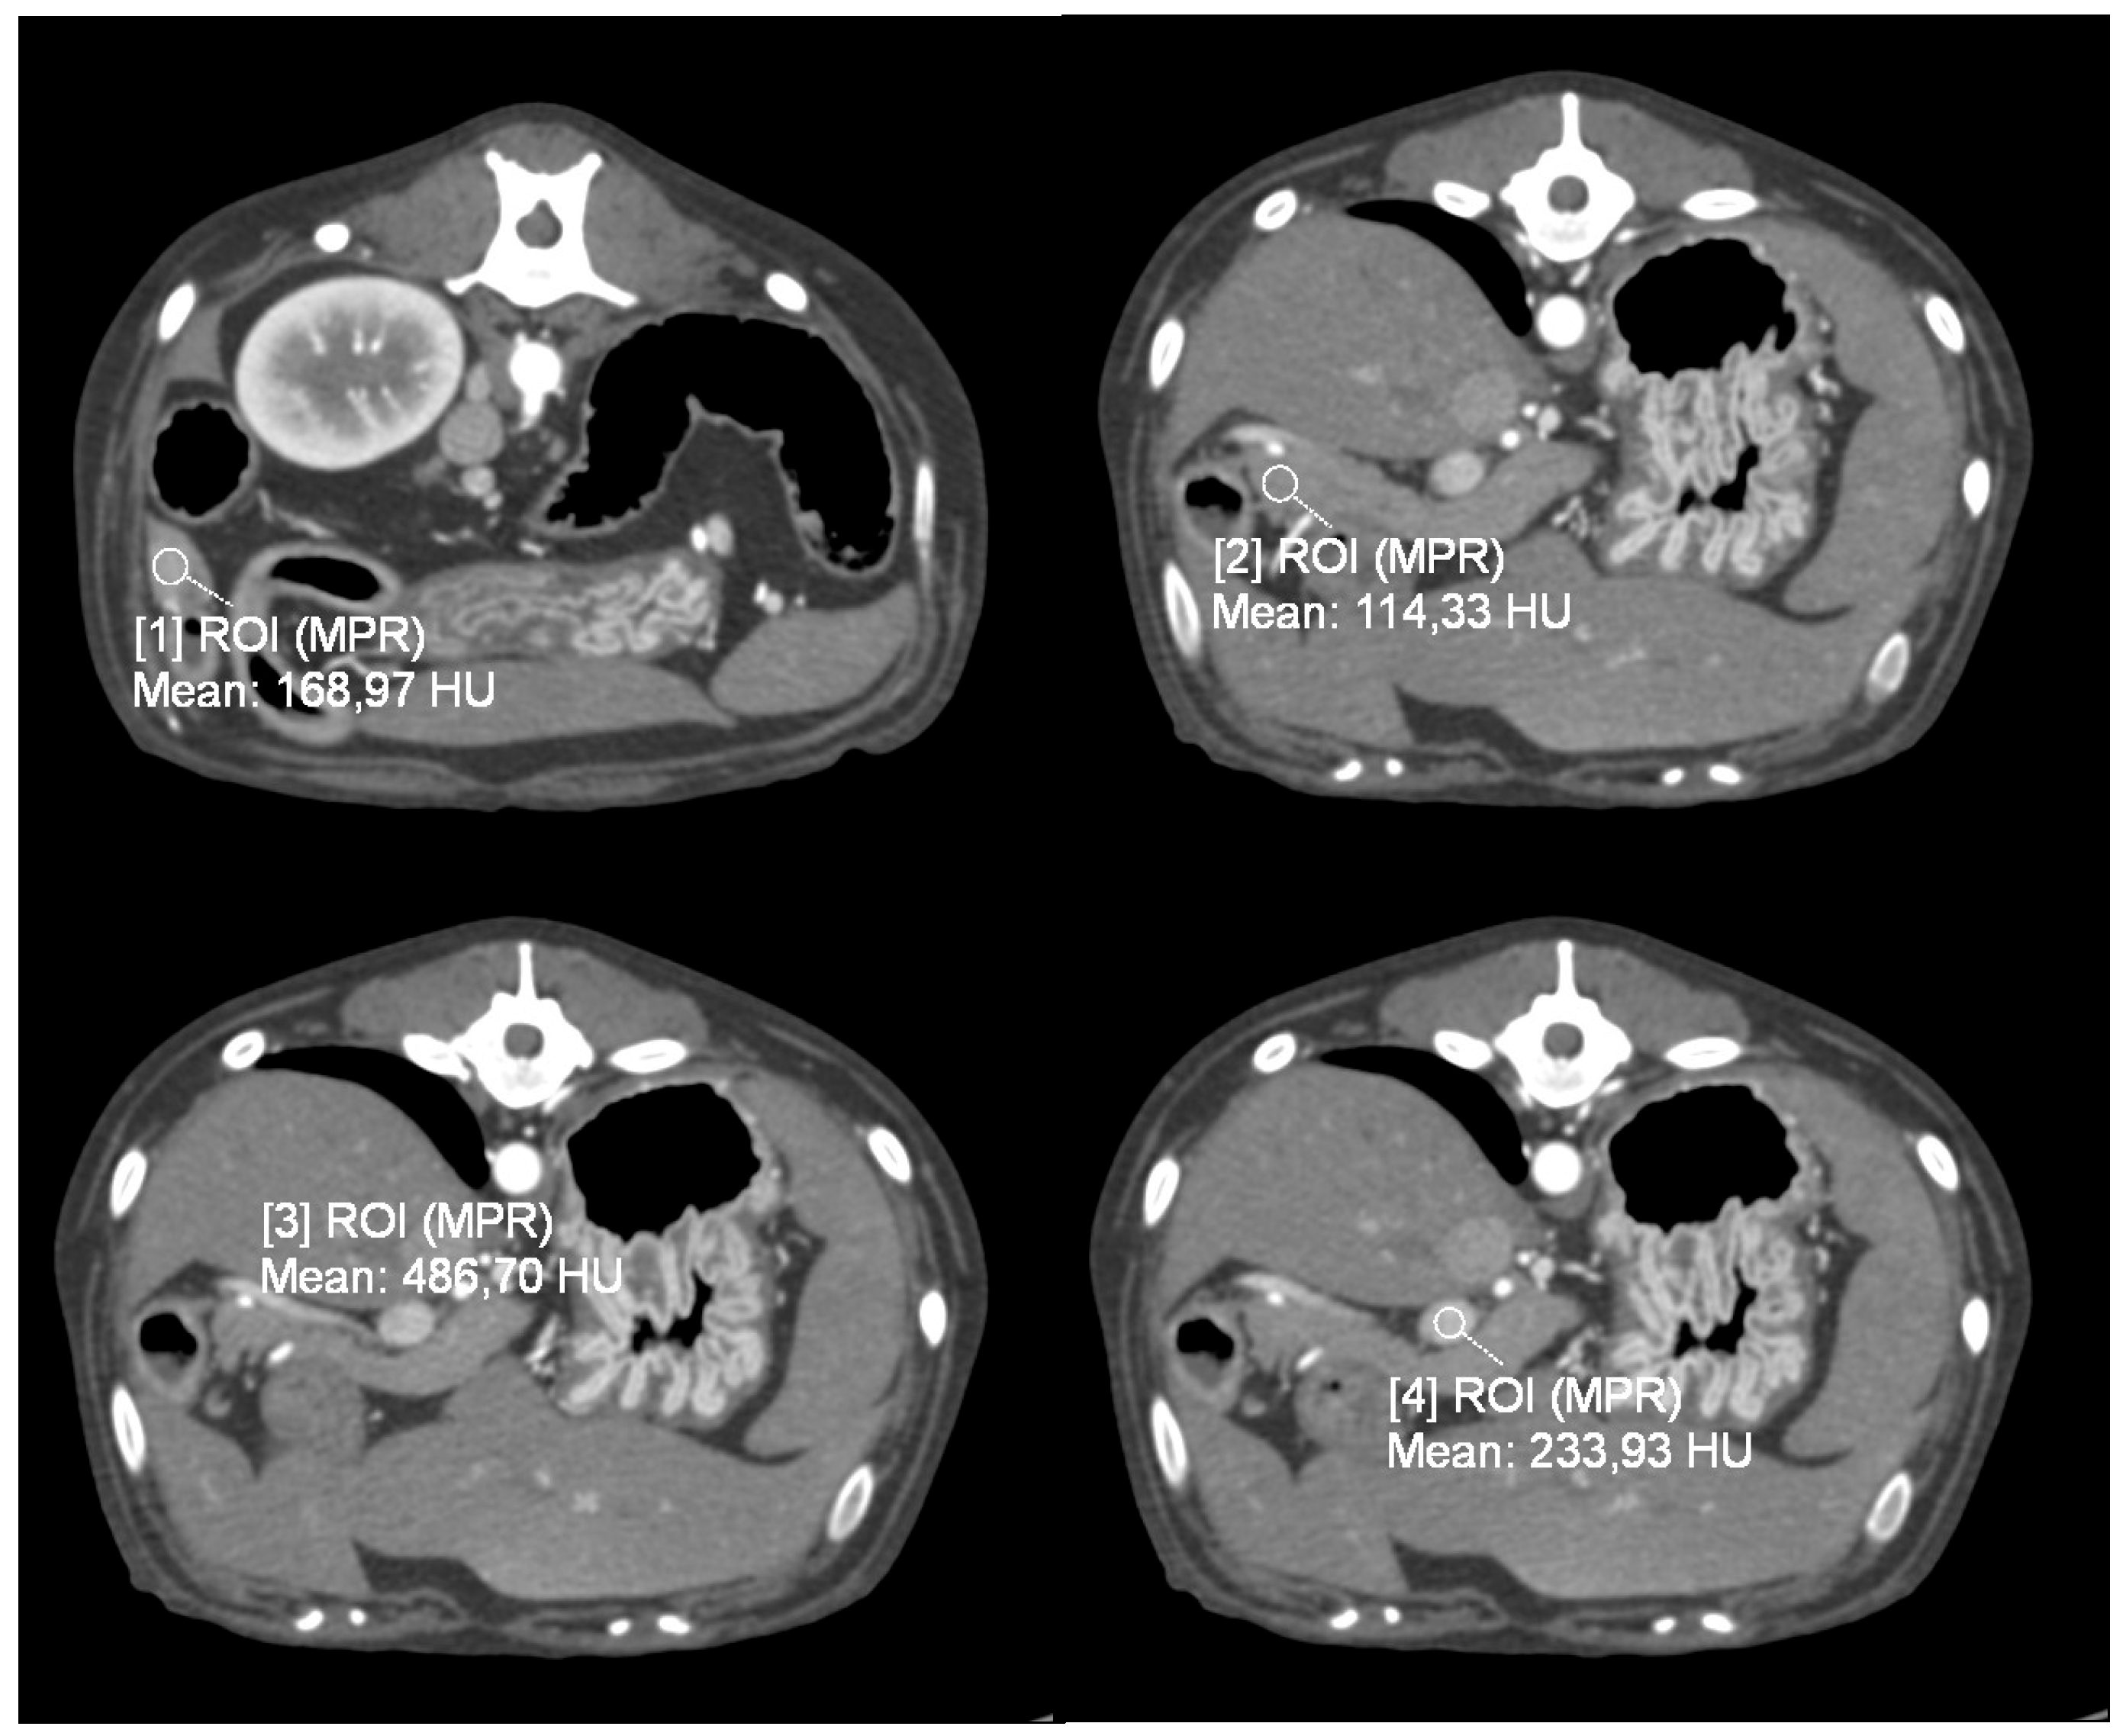

2.3.1. Quantitative Analysis

3.2. Quantitative Analysis